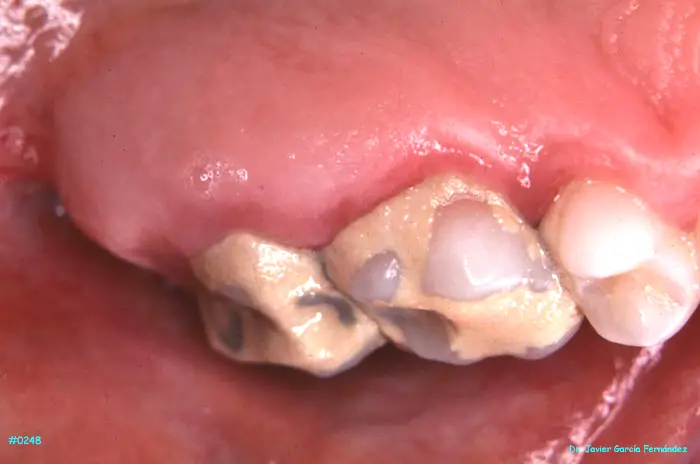

ATLAS DE CIRUGIA PERIODONTAL